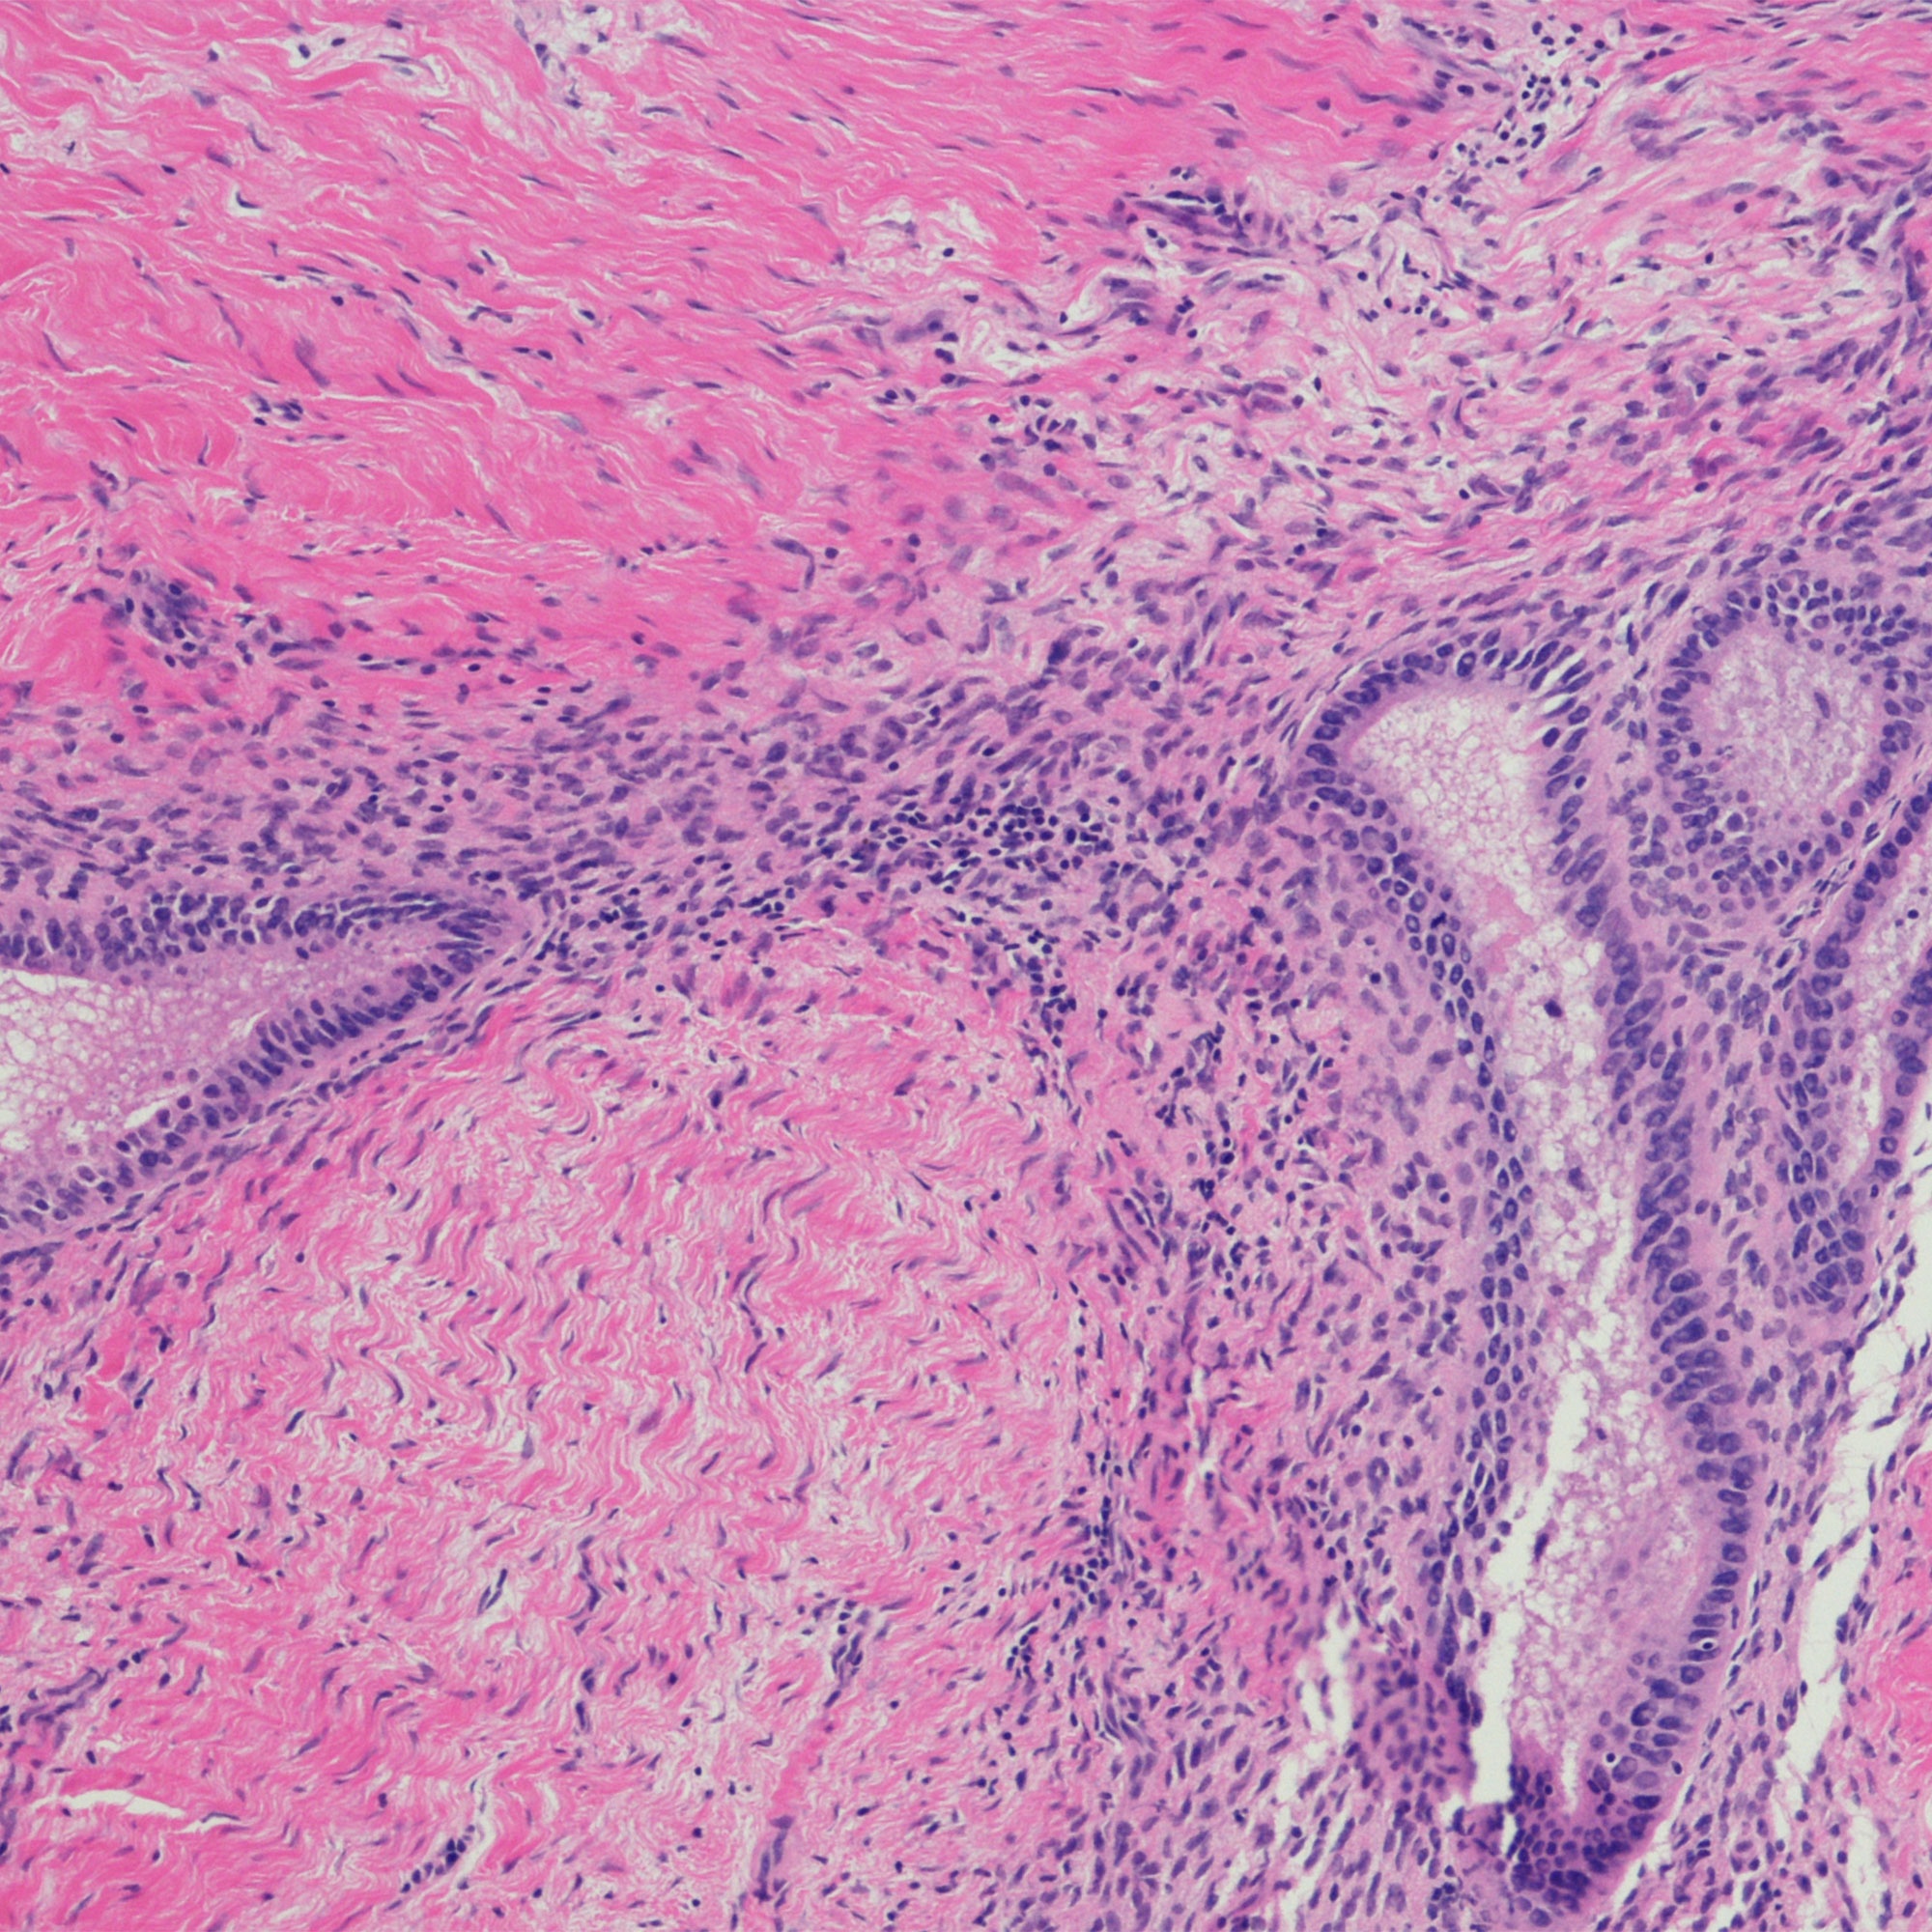

子宫内膜异位是一个条件,细胞就像那些在子宫内膜种植在子宫以外的。这些流氓细胞仍然被困在身体中,他们可以创建痛苦的粘连和疤痕在各领域的腹部和骨盆(有时在其他地方),包括在卵巢和输卵管。的位置和大小组织growths-as伤疤和adhesions-can创建物理堵塞的输卵管或卵巢完全封锁的精子从会议的鸡蛋,说蒙特Swarup,医学博士,a board-certified obstetrician-gynecologist (OB/GYN) in Chandler AZ, and founder of HPD Rx.

“当它是子宫内膜异位的人更难怀孕,它可以是由于炎症和结构性条件的副作用,”欧布斯博士说。子宫内膜异位症是一种炎症性的疾病,可以创建一个次优的环境精子遇到或卵细胞受精,她解释说。在某些情况下,输卵管炎症的封锁内精子进一步旅行到达卵子。在其他情况下,子宫炎症不允许受精卵正常连接并继续增长,欧布斯博士解释道。